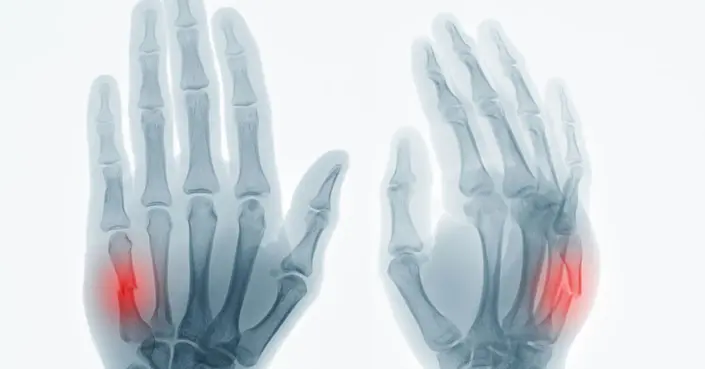

ما هي كسور اليد؟

تتكون اليد من عظام صغيرة ومعقدة، بما في ذلك عظام الرسغ (الكاربوس)، عظام المشط (الميتاكاربوس)، وعظام الأصابع (الكتائب). هذه العظام تدعم العضلات التي تحرك المعصم والأصابع، مما يجعلها ضرورية للحركة والوظيفة.

عندما تتعرض إحدى هذه العظام للكسر، نسمي ذلك “كسر اليد”. يمكن أن تتراوح شدة هذه الكسور من شقوق صغيرة إلى كسور متعددة ومعقدة، وكلها تتطلب رعاية طبية لضمان الشفاء الصحيح.

تشخيص كسور اليد

عند الشك في وجود كسر باليد، يقوم الطبيب بإجراء فحص سريري دقيق لليد المصابة، لتقييم مدى الألم والتورم والتشوه، والتحقق من سلامة الأعصاب والأوعية الدموية.

يعد التصوير بالأشعة السينية (X-ray) الخطوة الأساسية لتأكيد التشخيص وتحديد نوع الكسر وموقعه وشدته. في بعض الحالات، قد يطلب الطبيب فحوصات إضافية مثل التصوير المقطعي المحوسب (CT scan) أو التصوير بالرنين المغناطيسي (MRI) لتقييم الأضرار الأكثر تعقيدًا للأنسجة الرخوة أو العظام.